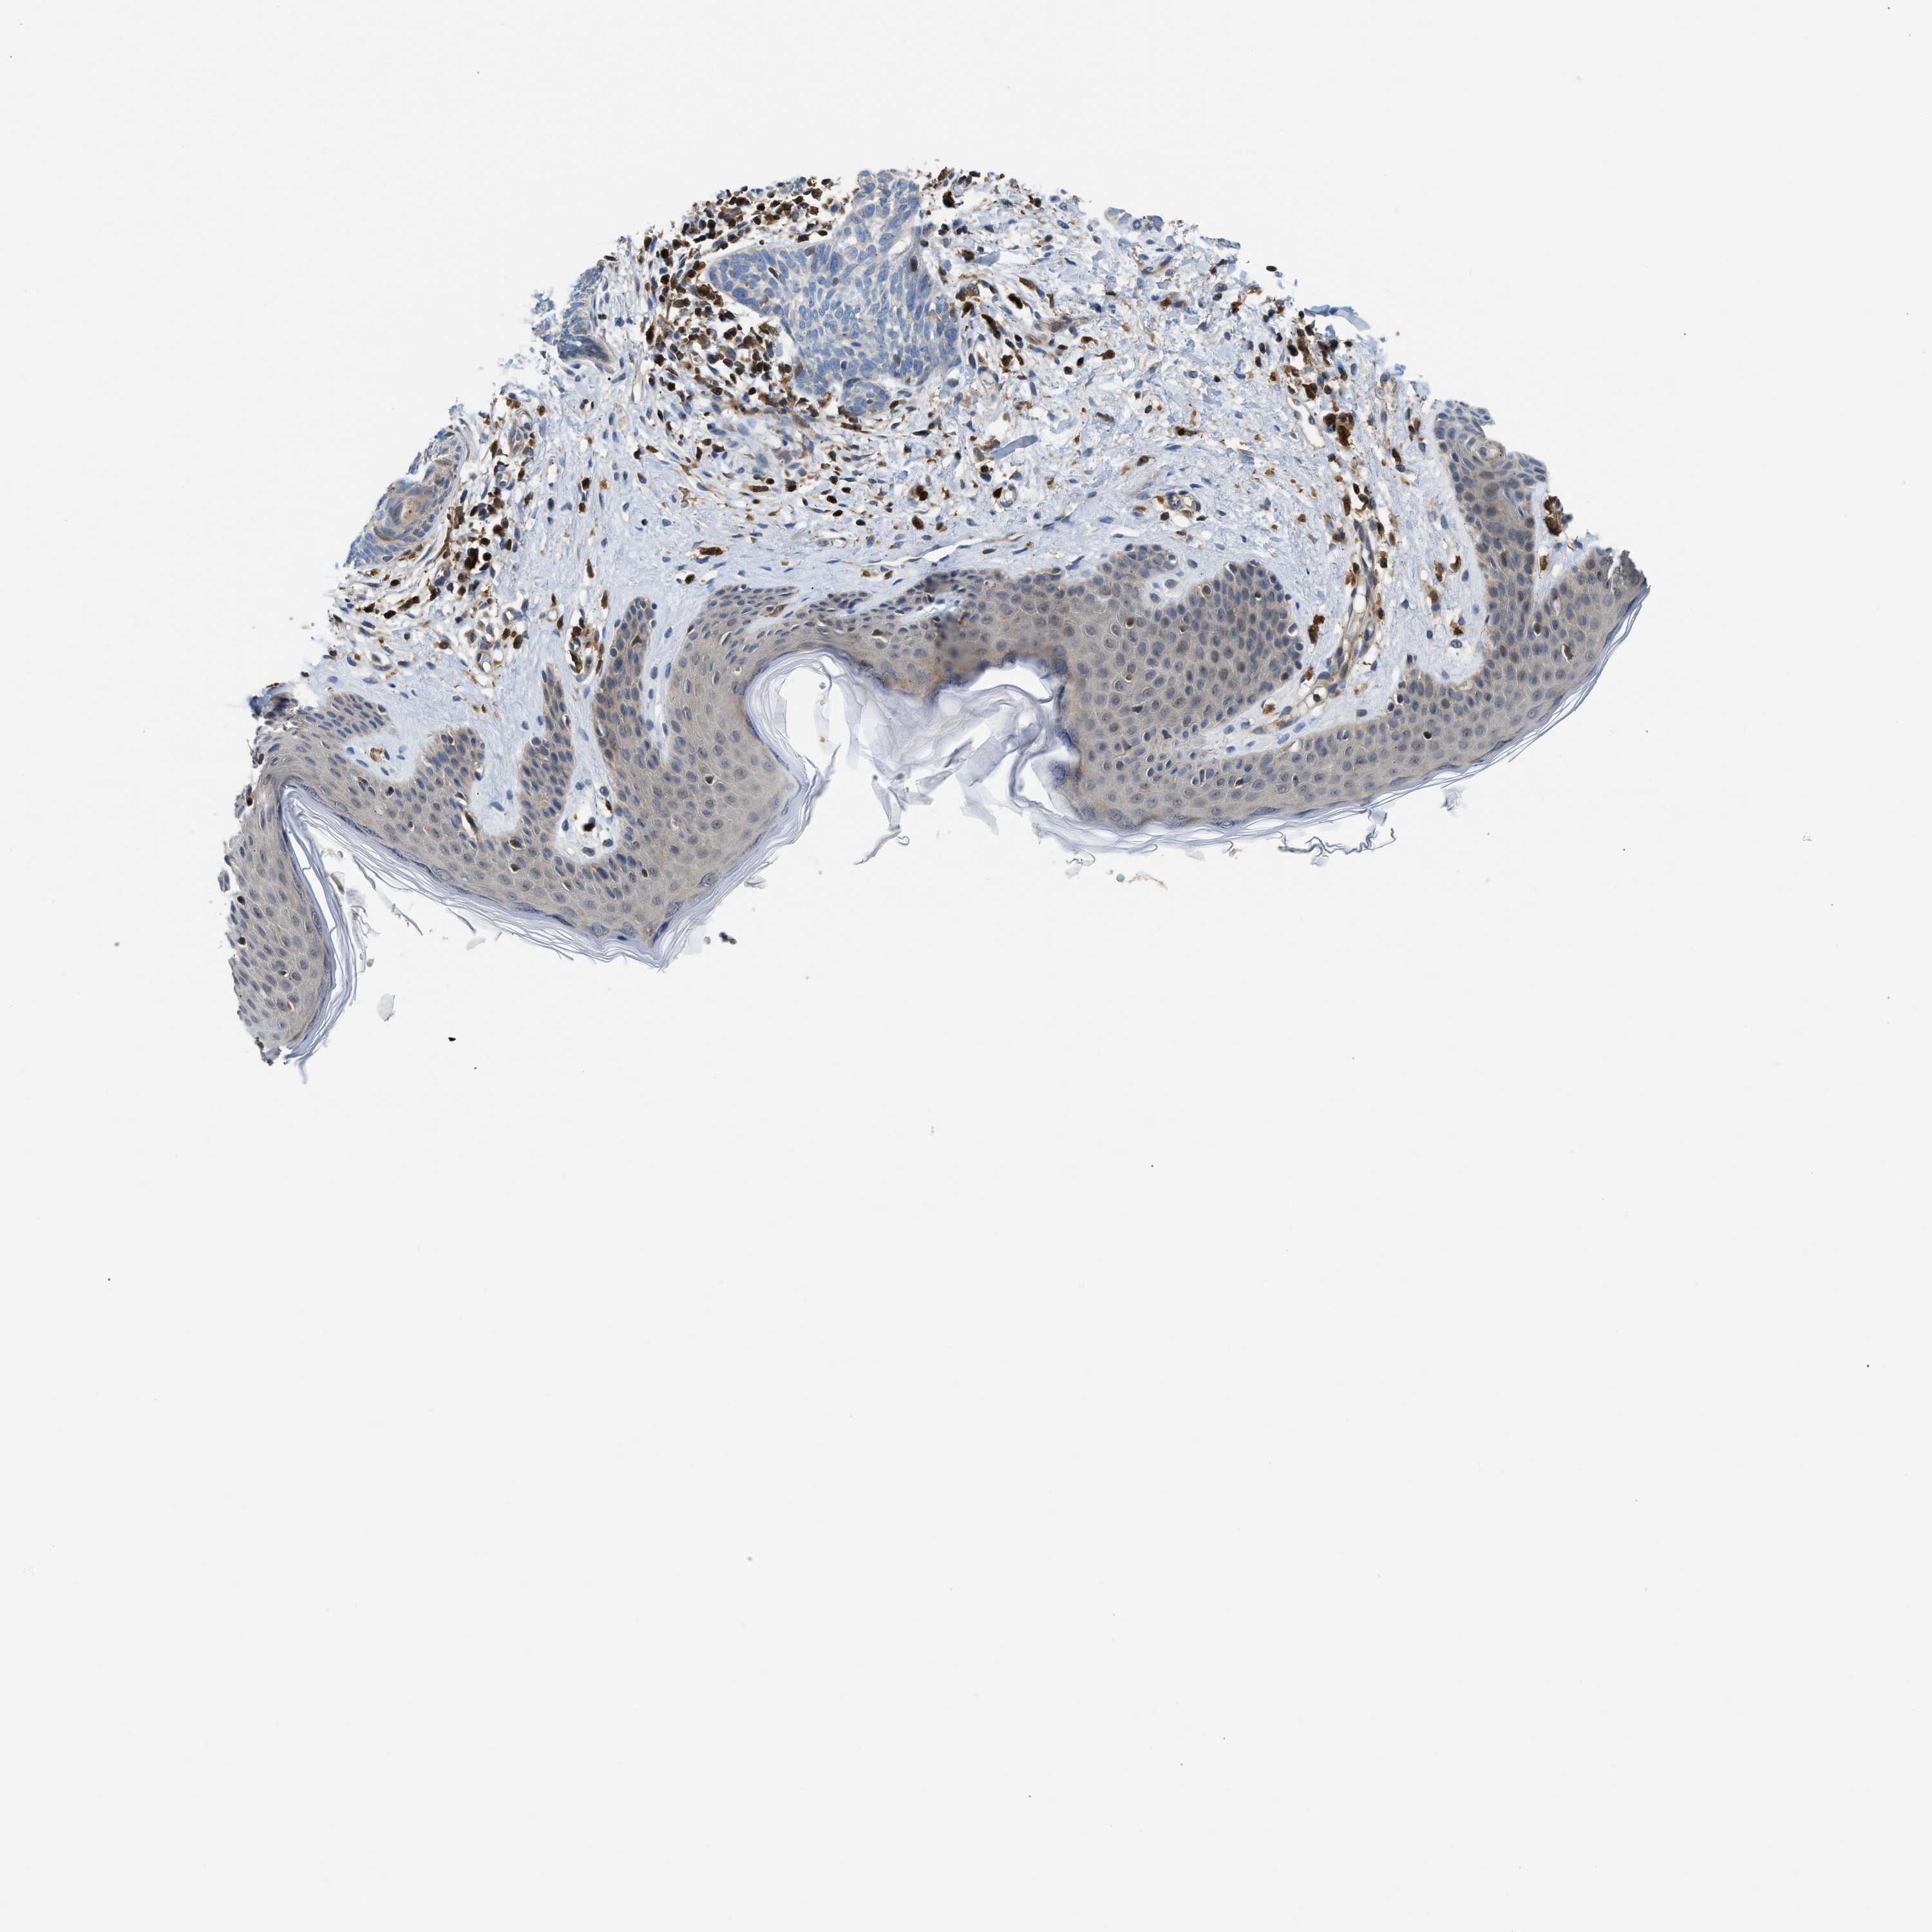

SKIN CANCER - Protein expressioni

A mouse-over function shows sample information and annotation data. Click on an image to view it in a full screen mode. Samples can be filtered based on level of antibody staining by selecting one or several of the following categories: high, medium, low and not detected. The assay and annotation is described here.

Antibody stainingi

Antibody staining in the annotated cell types in the current human tissue is reported as not detected, low, medium, or high, based on conventional immunohistochemistry profiling in selected tissues. This score is based on the combination of the staining intensity and fraction of stained cells.

Each image is clickable and will lead to virtual microscopy that enables deeper exploration of all samples and also displays staining intensity scores, fraction scores and subcellular localization as well as patient and tissue information for each sample.

Antibody HPA020514

Staining

High

Medium

Low

Not detected

Intensity

Strong

Moderate

Weak

Negative

Quantity

>75%

75%-25%

<25%

None

Location

Nuclear

Cytoplasmic/membranous

Cytoplasmic/membranous,nuclear

Squamous cell carcinoma, NOS